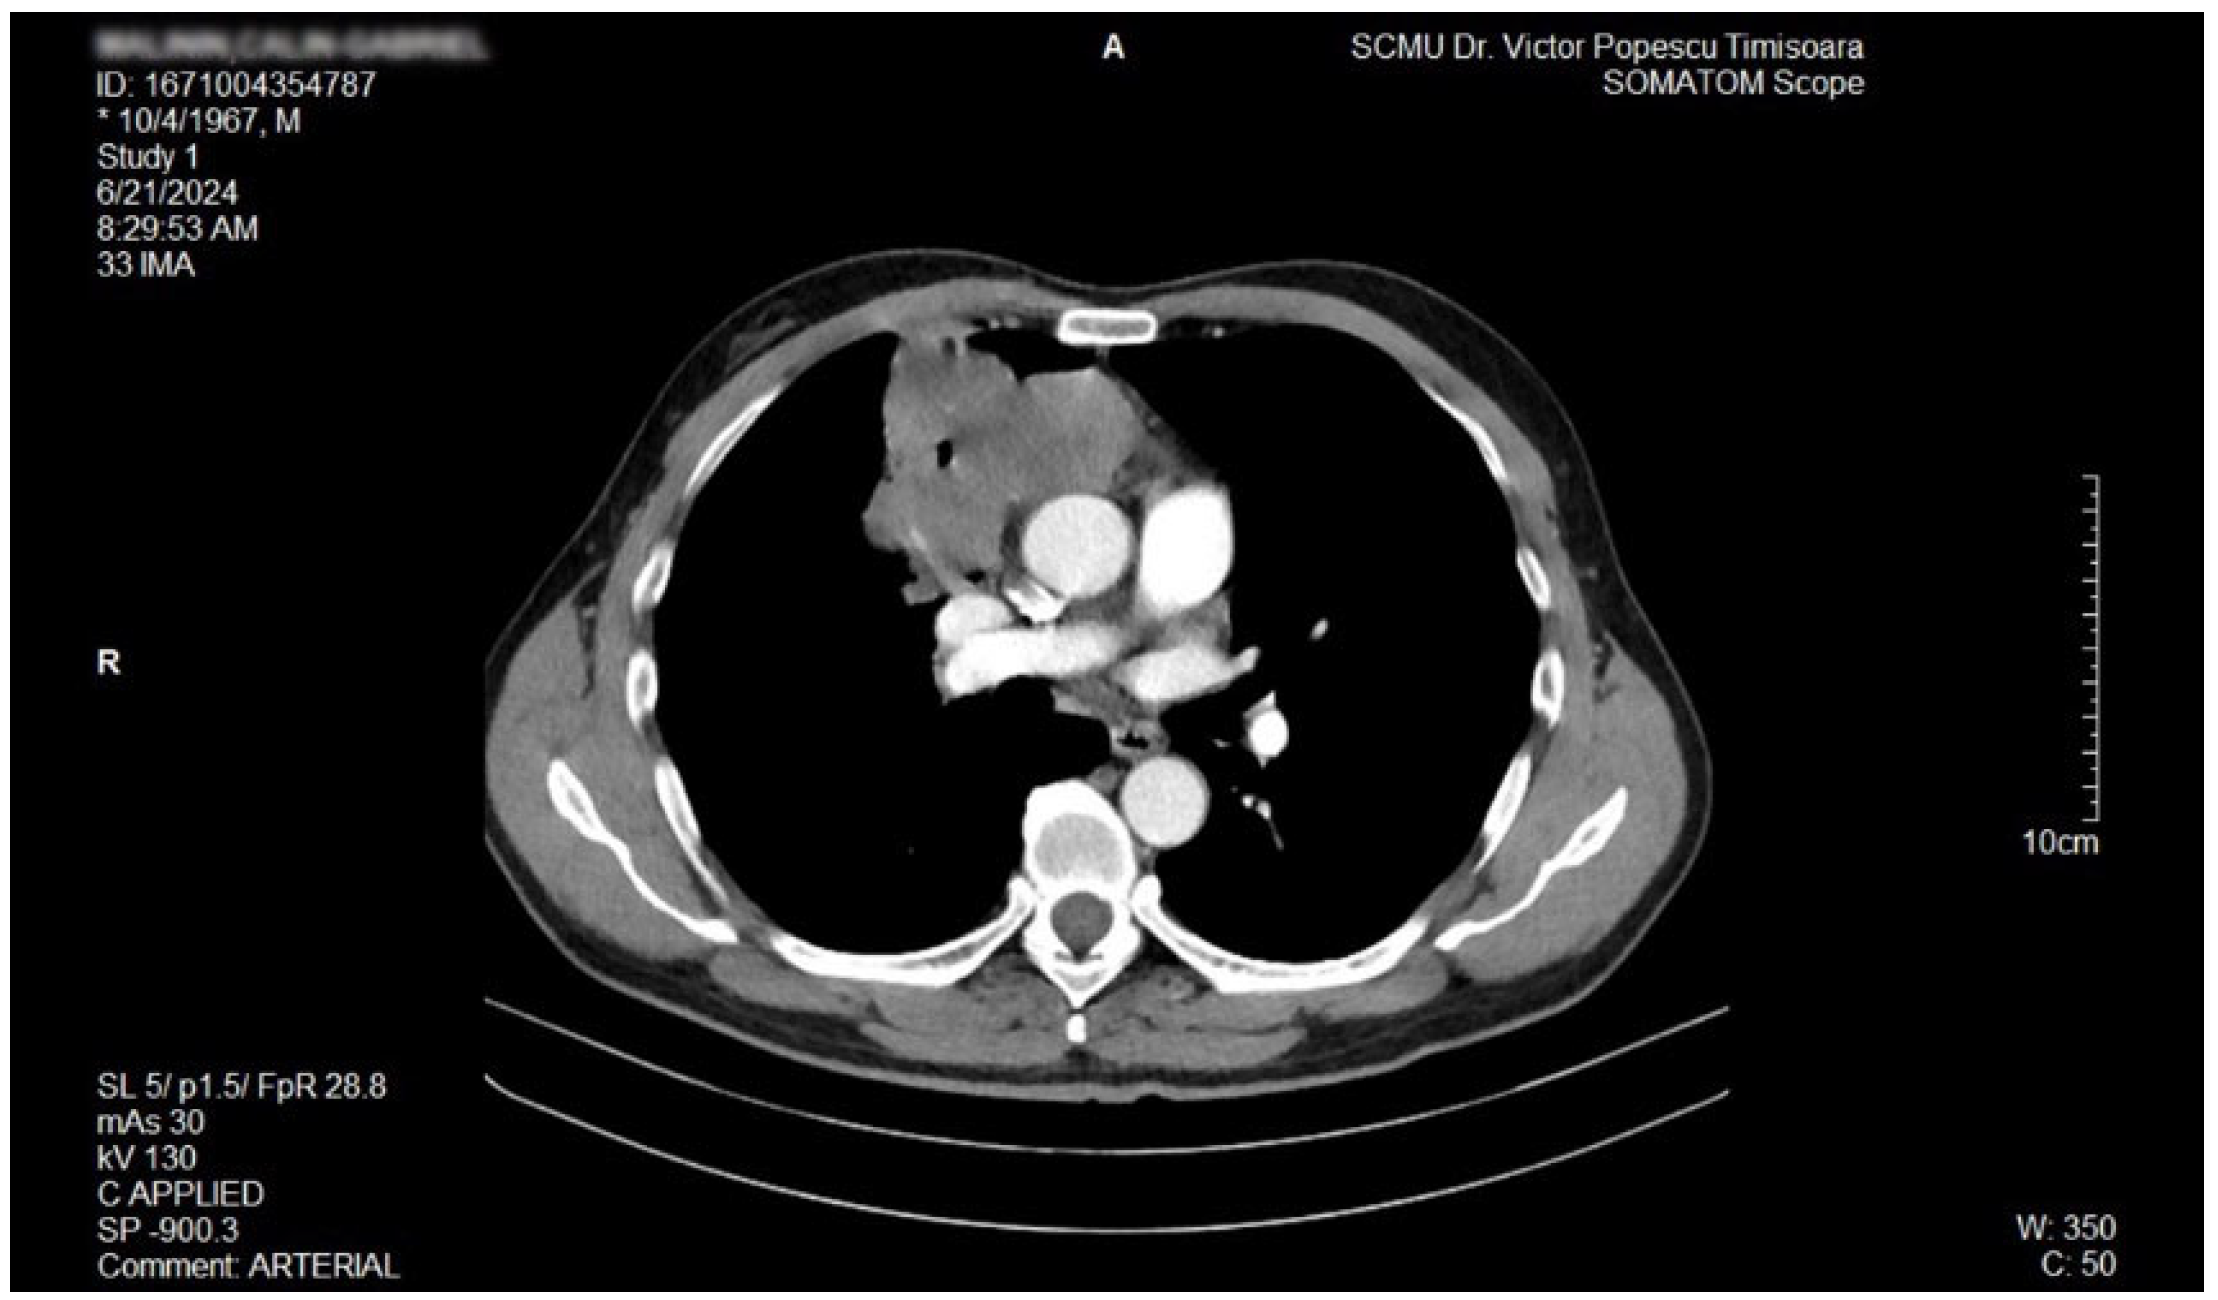

2. Case Report